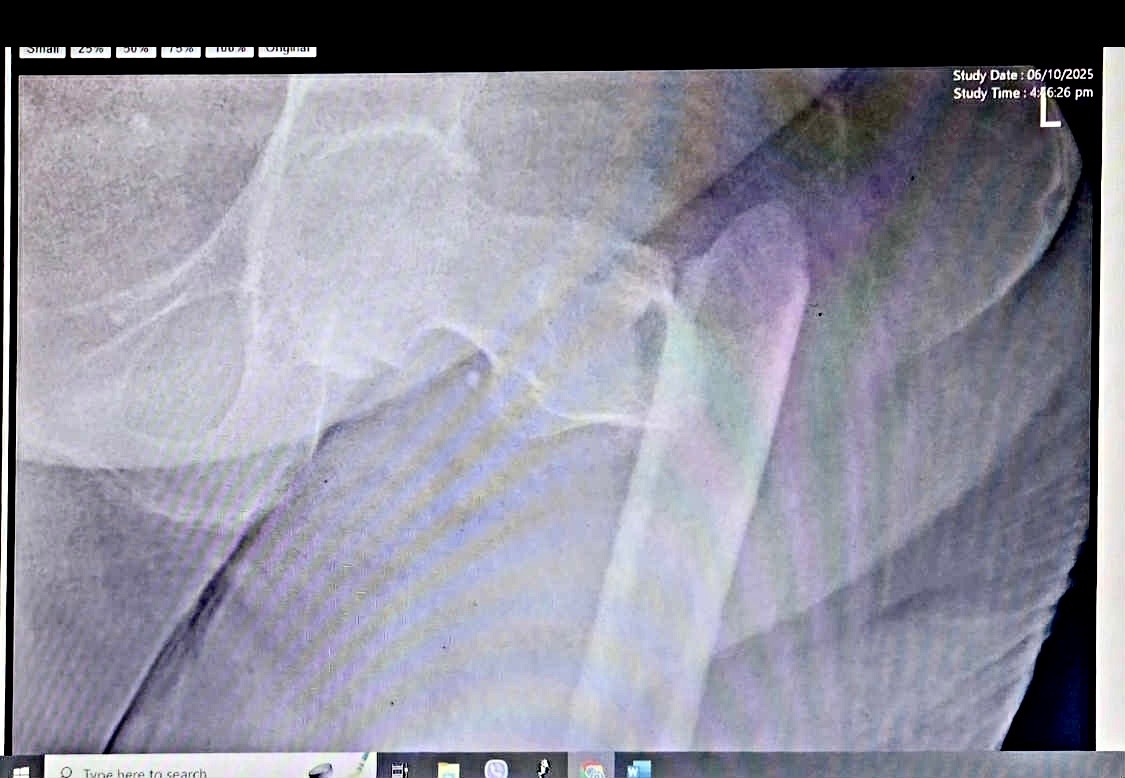

Back in October 6, 2025, Lola Susing had a ground-level fall at home. It all happened so fast. She was trying to get to the bathroom in the middle of the night, she got off balance despite the walker and fell. She cried out in pain, when my father and uncle heard her it was already too late. They rushed to help her — only to learn in the ER that she had fractured her left femur (thigh bone).

The doctors told us she needs surgery to repair the bone. It’s the best way for her to recover, relieve her pain, and regain even a bit of mobility. The estimated cost for the surgery, medications, and hospital stay is around ₱300,000.